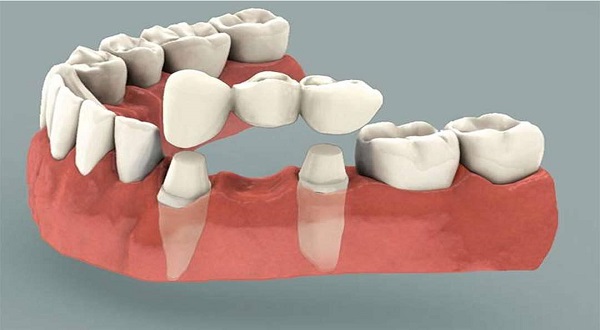

جسر الأسنان: متى يُستخدم؟

جسر الأسنان: متى يُستخدم؟ جسر الأسنان هو أحد الحلول الشائعة لتعويض الأسنان المفقودة. كثيرون يسمعون […]